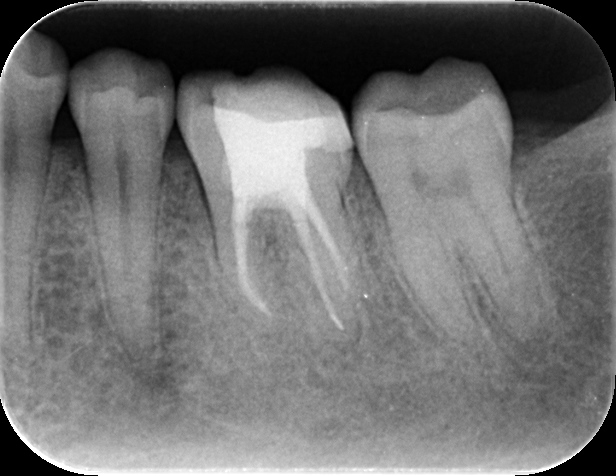

症例 下顎左側第一大臼歯予防的歯内療法 2025.09.10 主訴:海外赴任するため、根管治療をしっかり行い、セラミックの被せ物でやり直したい 背景:症状はないものの、脱離を繰り返す銀歯のやり直しと、精密根管治療を希望し当院へ 数ヶ月後に海外赴任を考えると、可及的速やかに歯内療法療法を終える必要性があった 状態:根尖病変は認めないが、不良な治療後であったため、説明と同意を得た後、歯内療法を行い セラミック修復を終えた 治療前デンタル 治療後デンタル 治療回数:2回 治療時間:各90分 治療費用:料金表参照 治療担当:野田哲朗 この記事のタイトルとURLをコピーする